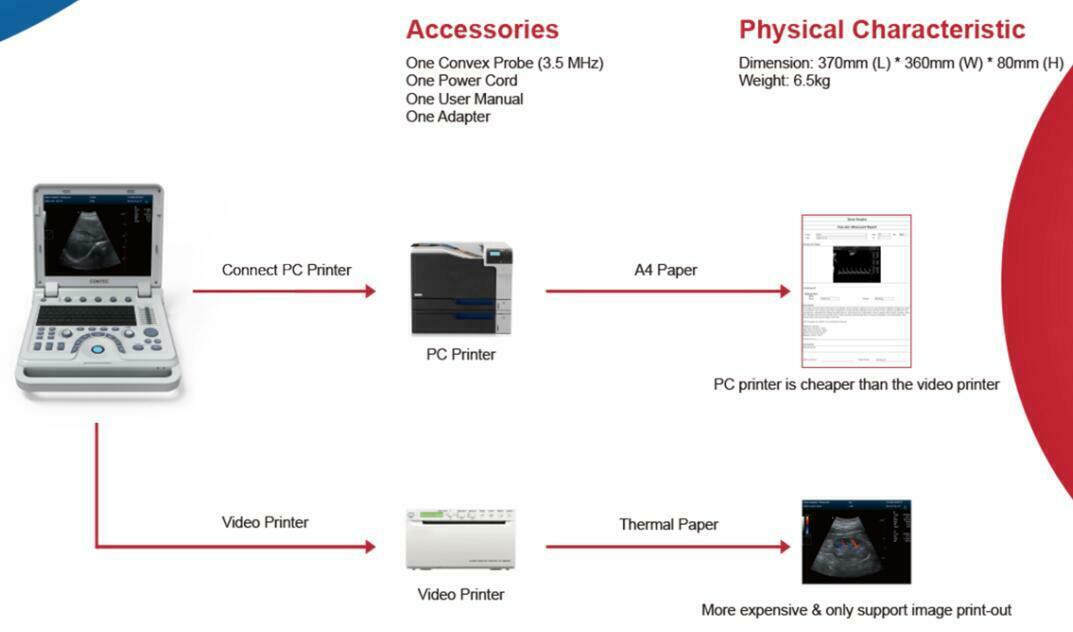

One of the key features of the Laptop Color Doppler Ultrasound is its portability. This means you can easily transport it between examination rooms or even take it off-site when necessary. Despite its compact size, it offers robust capabilities that rival larger, stationary units. Medical professionals appreciate the balance of convenience and high performance it offers.

Battery life is another significant advantage. The Laptop Color Doppler Ultrasound comes with a long-lasting battery, ensuring that it can function effectively for hours. This is particularly useful in emergency situations or in settings where power supply is unreliable. The battery can be quickly recharged, minimizing downtime and ensuring the device is always ready for use.

Furthermore, the machine is built to withstand frequent use. Its sturdy build means it can handle the rigors of daily operation in busy medical environments. Maintenance is straightforward, and the device is designed to be durable over time. This reduces the need for frequent repairs or replacements, ensuring cost-effectiveness in the long run.

Connectivity options are also impressive. The Laptop Color Doppler Ultrasound can easily connect to other devices and health information systems. This facilitates seamless data transfer and integration, enhancing workflow efficiency and patient record management. The ability to share diagnostic images and data quickly can significantly improve patient outcomes.